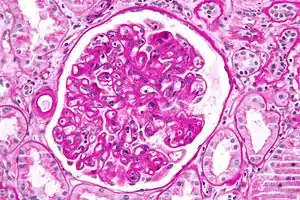

Initiated by preexisting humoral immunity, hyperacute rejection manifests within minutes after transplant, and if tissue is left implanted brings systemic inflammatory response syndrome. Of high risk in kidney transplants is rapid clumping, namely agglutination, of red blood cells (RBCs or erythrocytes), as an antibody molecule binds multiple target cells at once.

Developing with formation of cellular immunity, acute rejection occurs to some degree in all transplants, except between identical twins, unless immunosuppression is achieved (usually through drugs). Acute rejection begins as early as one week after transplant, the risk being highest in the first three months, though it can occur months to years later. Highly vascular tissues such as kidney or liver often host the earliest signs—particularly at endothelial cells lining blood vessels—though it eventually occurs in roughly 10 to 30% of liver transplants, and 10 to 20% of kidney transplants. A single episode of acute rejection can be recognized and promptly treated, usually preventing organ failure, but recurrent episodes lead to chronic rejection. It is believed that the process of acute rejection is mediated by the cell mediated pathway, specifically by mononuclear macrophages and T-lymphocytes. Histology of acute rejection is defined by dense lymphocytic cellular infiltrate as well as vasculitis of organ donor vessels.

Rejection detection

Diagnosis of acute rejection relies on clinical data—patient signs and symptoms but also calls on laboratory data such as blood or even tissue biopsy. The laboratory pathologist generally seeks three main histological signs: (1) infiltrating T cells, perhaps accompanied by infiltrating eosinophils, plasma cells, and neutrophils, particularly in telltale ratios, (2) structural compromise of tissue anatomy, varying by tissue type transplanted, and (3) injury to blood vessels. Tissue biopsy is restricted, however, by sampling limitations and risks/complications of the invasive procedure.[25][26][27] Cellular magnetic resonance imaging (MRI) of immune cells radiolabeled in vivo might—similarly to Gene Expression Profiling (GEP)—offer noninvasive testing.[28][29]